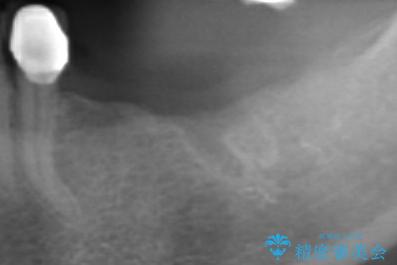

- 歯を失い噛むことができないことを悲観され来院されました。

他院で作製した入れ歯も嘔吐反射により気持ち悪くてはめていることができず、残存した右側の歯の負担は甚大です。

咬合機能を回復し、満足して食事を行えるようインプラント治療を計画します。